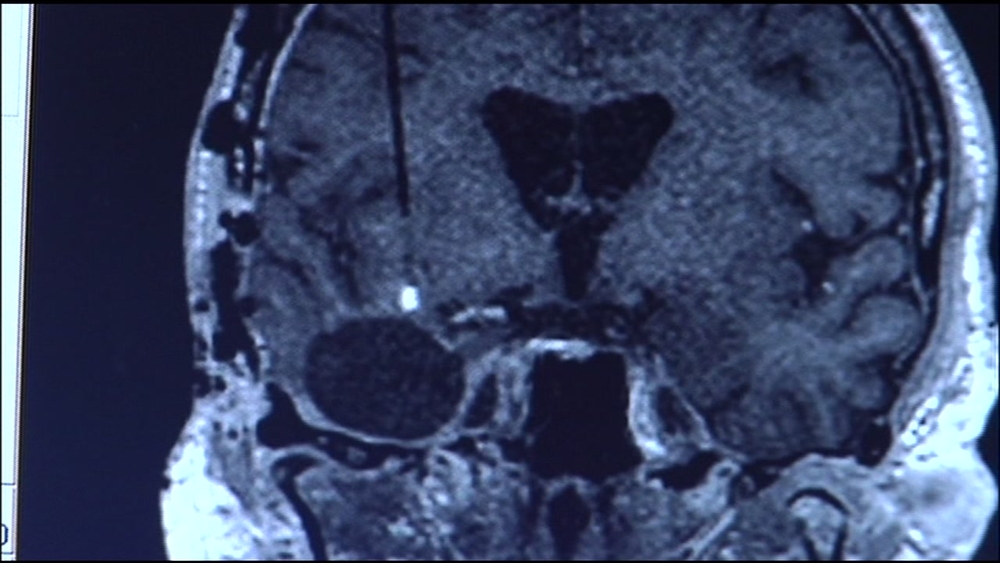

RELATED: Here's how patients say they reversed early Alzheimer's symptoms

We searched for and found women who embraced their protocols and either improved mental clarity or reversed early symptoms of Alzheimer's disease.